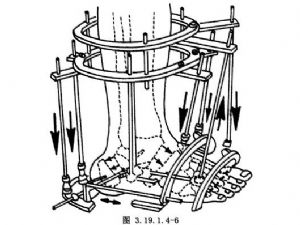

(2)V形截骨術:用以改變後足、中足和前足三者之間的位置關係。截骨部位一是在距下關節後方穿越跟骨體部;二是經由跗骨竇穿越距骨頸部和跟骨前部(圖3.19.1.4-6)。此截骨術的前提條件也是距下關節僵硬。通過截骨術可矯正足前部和後部對於足中部、小腿和地面的成角和旋轉畸形,即矯正其內翻、外翻、內收、旋後和旋前畸形。